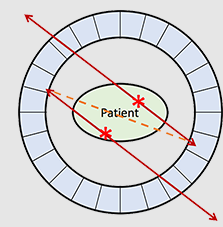

What is the relationship between each detector pair inside the ring of detectors in a PET camera?

Each detector works together with the detector opposite to it – allows it to pick up on a line of response

What is a line of response?

When the photons from an annihilation reaction are emitted, they will travel in opposite directions of one another – makes a 180-degree line almost

How does a ‘dot’ from our image translate from the reaction at the PET detectors?

The detectors create a dot on our scanned image from the point at which the 2 photons are overlapping – or where they cross each other in the ring of detectors but we still need more information to specifically determine it!

What is needed in order for the PET detectors to determine where an annihilation reaction occurred on a line of response?

Requires multiple line of responses to figure out where the intersection of where the annihilation reaction took place